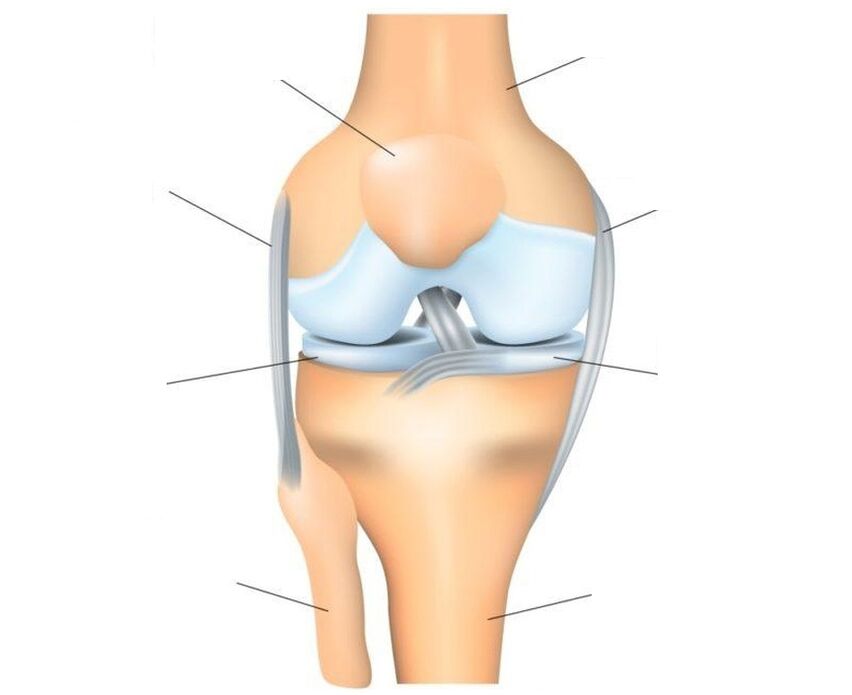

The knee joint is the most complex joint, because it carries the main load.Structure: three bones (femur, tibia and patella form one trochlear joint, which consists of two interconnected joints: femorotibial (tibiofemoral) and femoral-patellofemoral (patellofemoral).

The patella is a flat sesamoid (an accessory in the joint) bone that is attached to the head of the femur, slides in its concave groove and acts as a block.Structural features: the front surface of the patella is covered with periosteum, the back surface, which connects to the femur, is covered with hyaline cartilage.The patella is strengthened by ligaments: main and lateral - vertical (upper and lower) and horizontal (lateral - internal and external).

O transmits the strength of the quadriceps femoris muscle to the musculoskeletal formations of the lower leg, ensuring extension of the lower leg at the knee joint.The surface of the bones that form the joint is covered with cartilage, which acts as a shock absorber.Additional shock absorbers that protect the joint from injury are two crescent-shaped cartilaginous menisci located between the femur and the tibia.The joint is held in its proper position by ligaments, tendons and the surrounding capsule.

Injuries and diseases affect different joint tissues.Not everyone can get sick.Therefore, the cartilage tissue does not have nerve endings and therefore can be destroyed imperceptibly and painlessly.But the ligaments and synovial membrane have many nerve endings and in case of injury or inflammatory processes they immediately start to react, which manifests itself in the form of severe pain.With significant destruction of the articular cartilage, pain may be associated with involvement of the periosteum, the outer layer of bone that has good innervation, in the process.